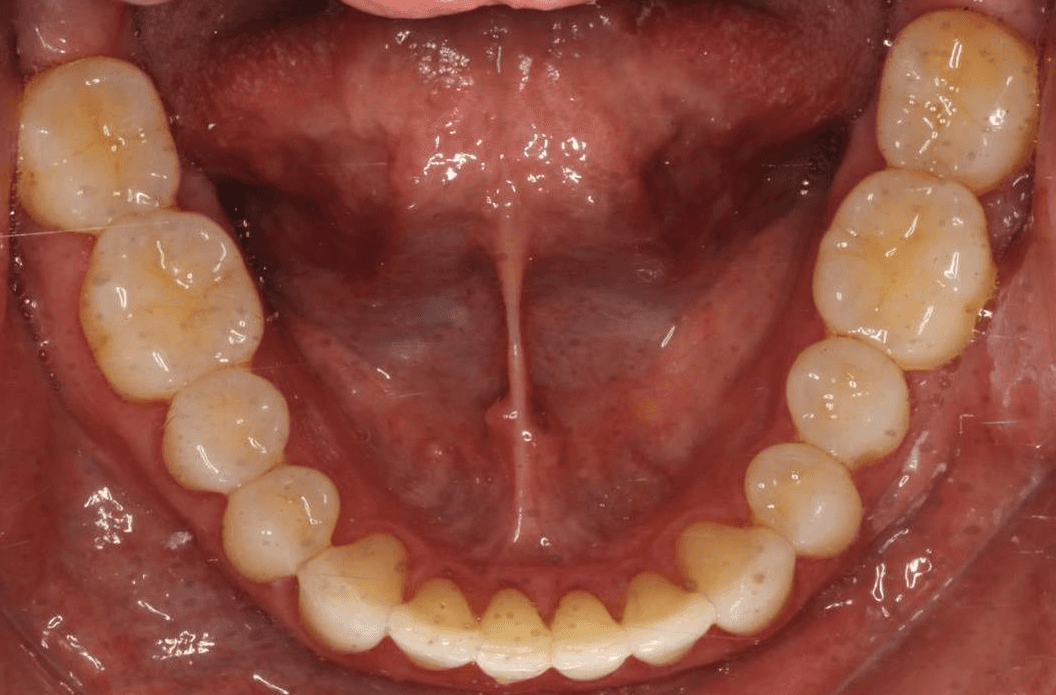

INTRAORAL